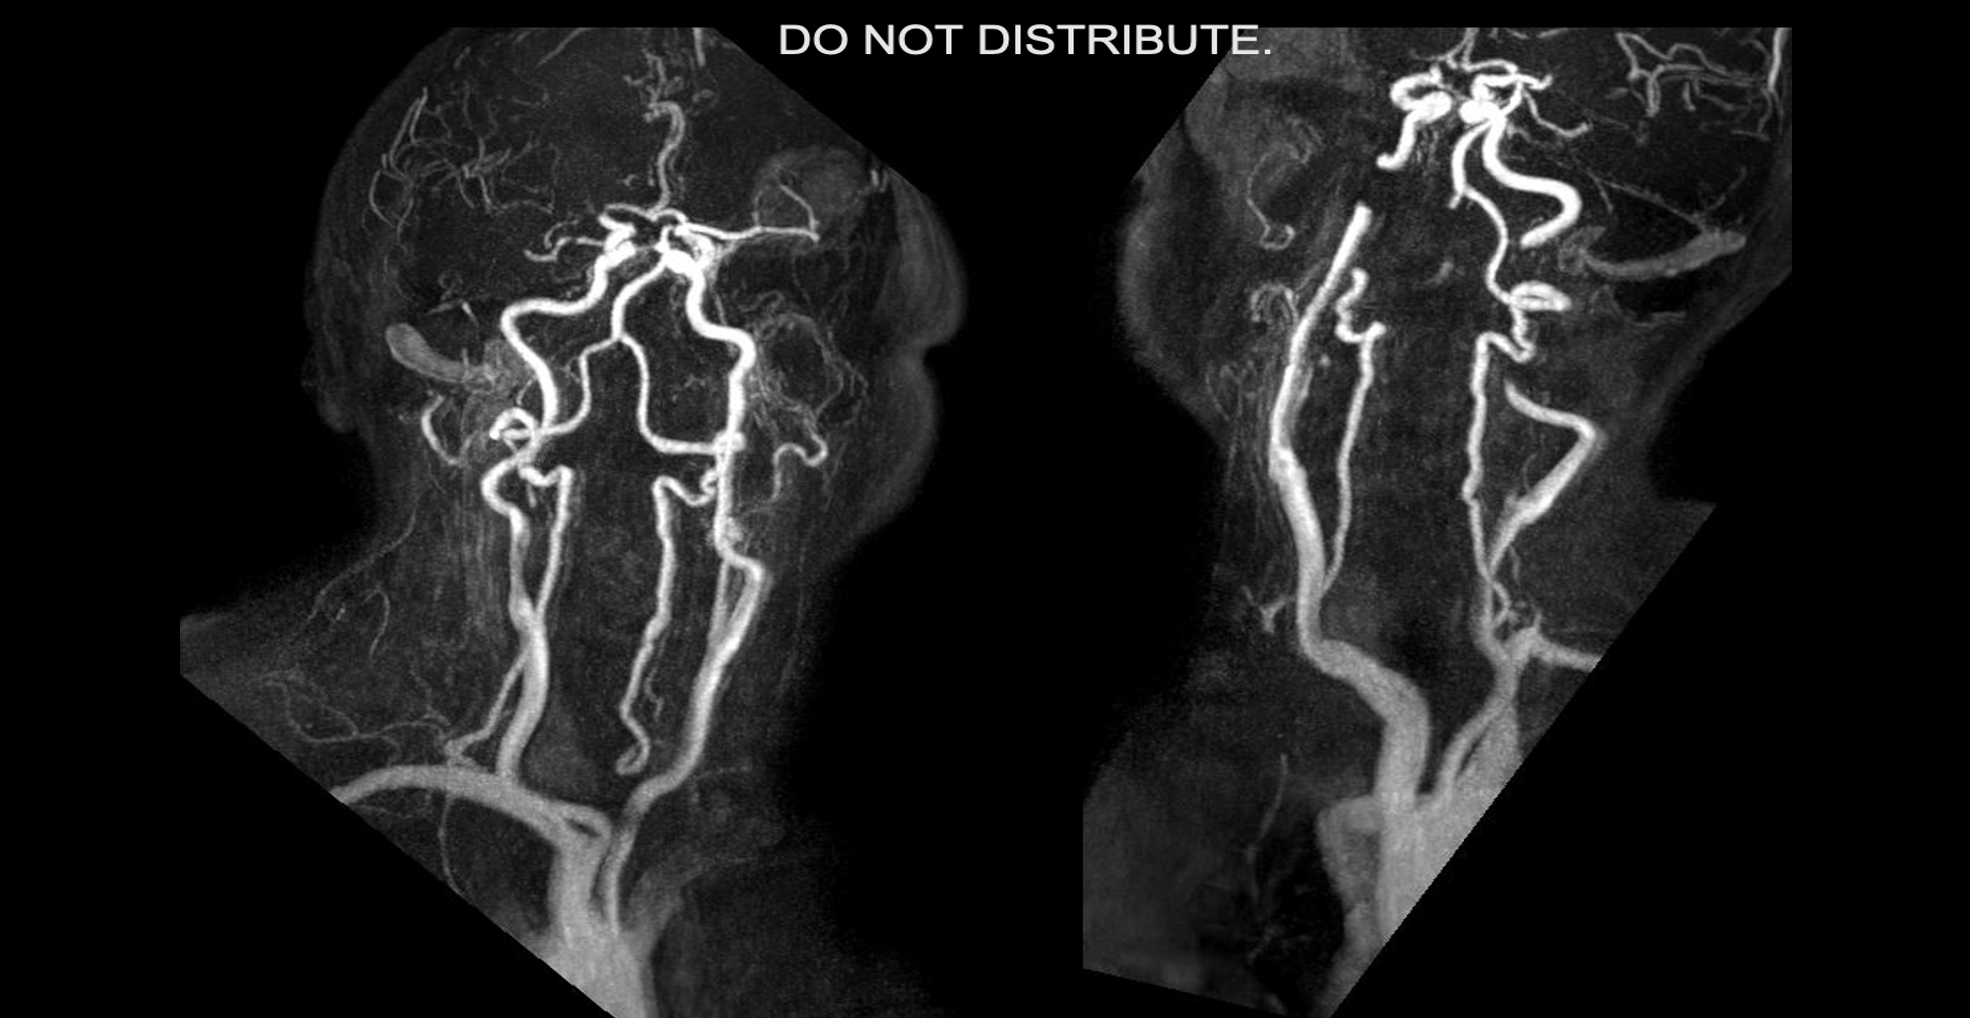

Multiple sclerosis (MS) is an autoimmune disease in which the immune system attacks the myelin sheath of neurons, leading to progressive neurological symptoms. Anti-CD20 monoclonal antibodies have emerged as highly effective treatments for relapsing MS (RMS), with Ocrelizumab (OCR) being the standard approved therapy and Rituximab (RTX) used as an off-label alternative. The impact of anti-CD20 therapies on immune markers remains understudied, though deficiencies are frequently observed and may be associated with increased risk of infection. Our objective is to compare lymphocyte, neutrophil, and immunoglobulin levels in OCR- versus RTX-treated persons with RMS.

This retrospective chart review included patients with confirmed RMS who initiated treatment with OCR or RTX between January 2017 and June 2023, and who had at least one pre-treatment complete blood count (CBC) and one post-treatment CBC and immunoglobulin panel available. Treatment assignment was primarily influenced by insurance coverage. Lymphocyte, neutrophil and immunoglobulin levels (IgG, IgA, IgM) from before and after treatment initiation were collected, where available. Deficiencies were defined as values below the lower limit of normal as per local laboratory guidelines. The statistical approach comprised three complementary analyses:

• Fisher's Exact Test compared the prevalence of new-onset deficiencies between OCR and RTX groups at 2, 4, and beyond 4 years of treatment.

• Kaplan-Meier survival analysis estimated deficiency-free probability over time, with Log-rank Tests comparing treatments and Cox Proportional Hazards Models quantifying relative risk.

• Linear Regression with Mixed-Effects Models were used to illustrate laboratory value trajectories.

RESULTS

A total of 634 patients were included (OCR=386, RTX=248), with the OCR group being slightly older (44.7±9.9 vs 42.9±11.1 years, p=0.043) and having longer treatment duration (67.7±17.9 vs 48.2±18.8 months, p<0.05), while the RTX group had significantly greater pre-treatment immunoglobulin panel availability (39.9% vs 7.5%, p<0.05) (Table 1).

No significant differences were observed between the OCR and RTX treatment groups at 2, 4, and more than 4 years, although both groups showed a progressive accumulation of immune marker deficiencies over time (Figure 1). By year 4 of treatment, deficiencies were most common in IgM (26-31%), followed by IgG (12-13%), IgA (4-7%), lymphocytes (5.3-5.4%), and neutrophils (0-1.7%).

Screen shot 2025 05 06 at 8.17.56 pm Noun slideshow grey Screen shot 2025 05 06 at 8.18.17 pm Screen shot 2025 05 06 at 8.18.33 pm

Figure 1. Prevalence of immune marker deficiencies across treatment duration.

Bar charts showing the percentage of OCR- versus RTX-treated patients developing new immunoglobulin and cell count deficiencies at three time points (2, 4, and >4 years of treatment).

Survival analysis reveals that RTX is associated with significantly higher risks of developing IgM deficiency (HR=1.6, p=0.016, 95% CI 1.09-2.34) and IgA deficiency (HR=2.38, p=0.048, 95% CI 1.01-5.63) compared to OCR, despite similar cross-sectional prevalence rates. Linear regression analysis confirms RTX causes significantly faster IgM depletion (p=0.0044 for slope difference, p < 0.05 in mixed model, Figure 2).

Igm trajectories Noun slideshow grey Igg trajectories Iga trajectories Neutrophil trajectories Lymphocyte trajectories All parameters survival curves

Figure 2.  Longitudinal immune marker trajectories by treatment regimen

Spaghetti plots show individual patient data (thin lines) and demonstrate considerable inter-patient variability. Treatment-specific regression lines (thick lines, with shading that demonstrates 95% CI) show overall trends. Deficiency threshold is represented by red dotted lines. Kaplan-Meier curves depict survival analysis.